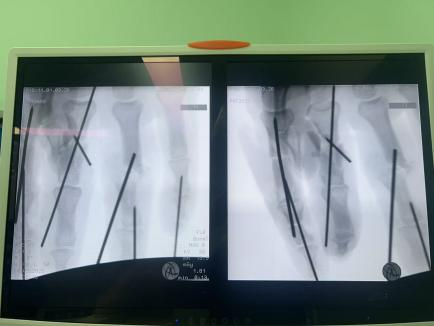

面对这些困难,许攀峰团队没有却步,沉着应战。他们先是为骨折的手指进行精准内固定,重建骨骼支撑;随后,在显微镜下,一根根寻找断裂的血管、神经和肌腱——清创、修剪、吻合、通血……每一步都如履薄冰,每一次打结都需屏息凝神,手术室内,寂静无声,只有时钟的滴答声在空气中回荡,仿佛在为这场生命的接力默默计时。

当第一根吻合的血管重新恢复搏动,苍白的手指逐渐转为红润时,手术室内紧张的气氛稍稍缓和。但团队成员们深知,战斗还远未结束,还有两根手指等待着他们的救治。

1小时、2小时、3小时…… 时间在寂静中流逝,显微镜下,一双双手在无声地忙碌着,他们的动作娴熟而精准,如同在跳一场无声的生命舞蹈。终于,将近5个小时后,最后一针缝线完成。松开止血钳,所有再植的手指瞬间恢复红润,指腹饱满,毛细血管反应灵敏——手术成功了!这一刻,手术室内压抑的气氛瞬间被打破,许攀峰团队成员们脸上露出了欣慰的笑容。